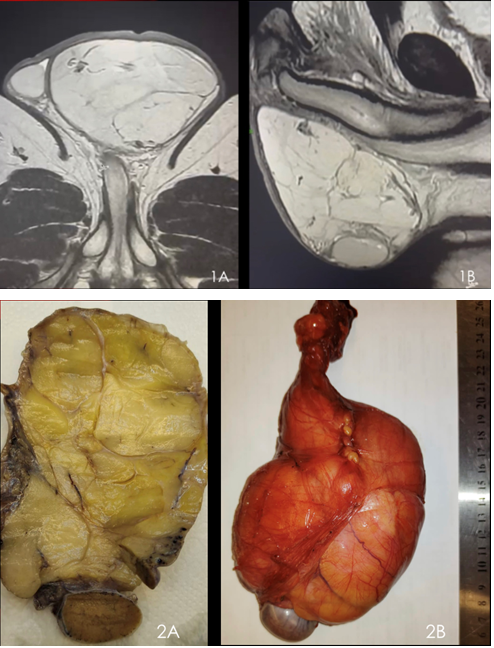

Well-differentiated “lipoma-like” giant paratesticular liposar-coma: a case report

Victor Teixeira Dubeux, Tadeu Campos, Jan Michael Sobel, Lucas Shulze Rodrigues, Pedro Ferrer

30-33